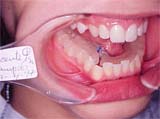

Fig. 4

Entretanto, ao observar a arcada inferior, constatamos a falta de espaço para o 43 e o forte apinhamento dos incisivos, demonstrando a necessidade de intervenção primeiro nesta arcada.

Optamos então por iniciar distalizando o setor 4.